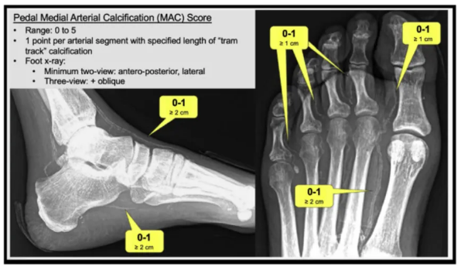

结合微循环功能评估和MAC评分

评估工具发展:

传统工具:ABI、TBI、TcpCO₂、SPP、PVR

新型有前景工具:植入式微氧传感器、灌注血管造影、激光散斑成像、足部动脉加速时间(PAT)